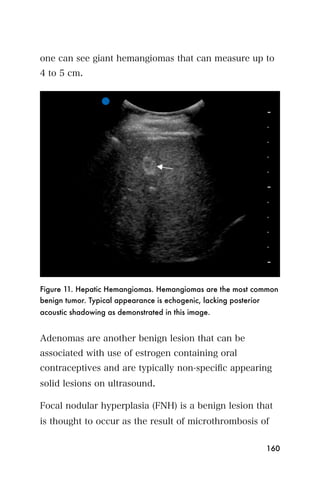

3). The uterus is shaped like a bean. On the screen, it

appears gray, or moderately echogenic. The